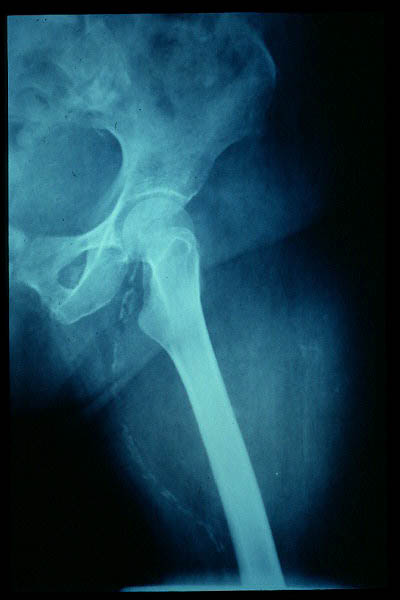

Fractura de cuello de fémur.

Fractura de cuello de fémur